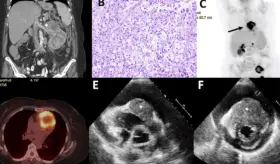

El cuadro se caracterizó por neumonía necrotizante, aleteo auricular con respuesta ventricular rápida, insuficiencia cardíaca biventricular y formación de trombos intracardíacos bilaterales.

La compresión de la arteria coronaria principal izquierda (LMCA) por dilatación de la arteria pulmonar representa una complicación subdiagnosticada de la hipertensión pulmonar severa, con prevalencia del 6%.